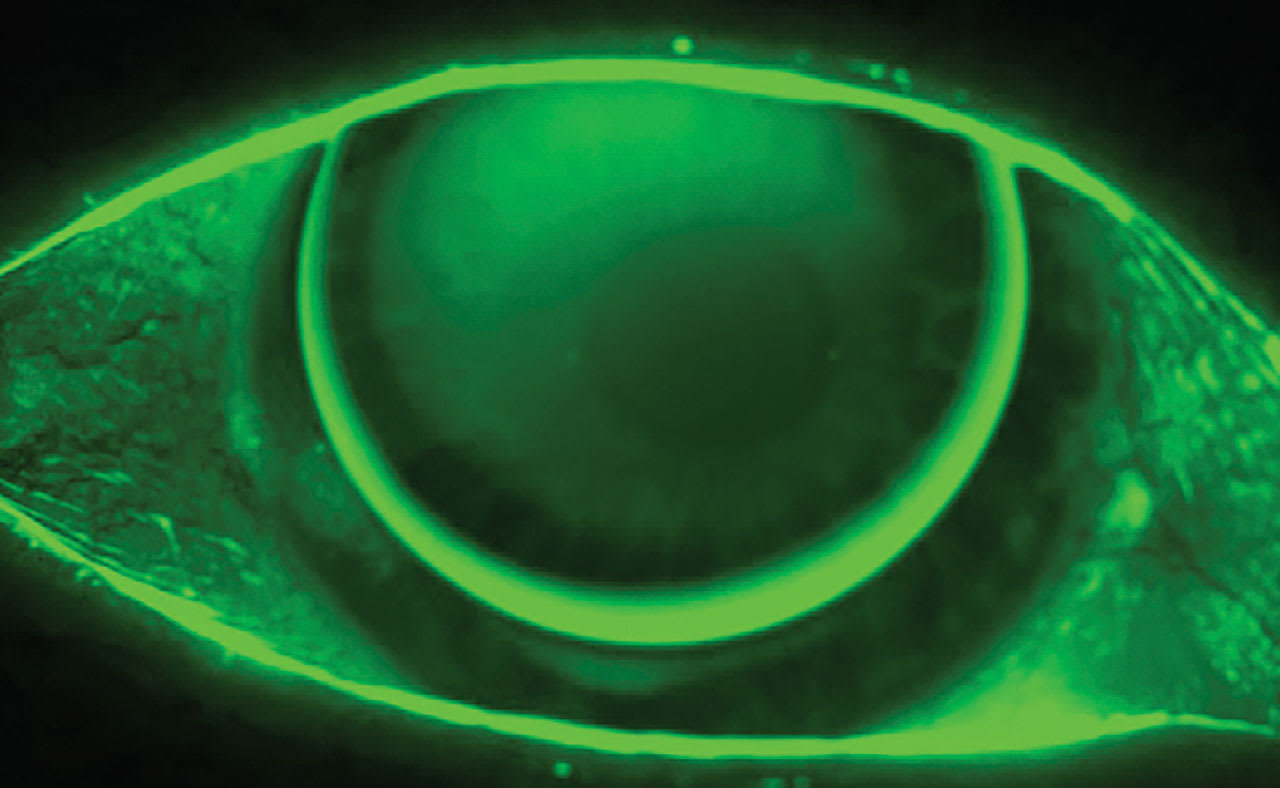

Figure 1 shows the appearance of the first lens, with the lens position still a little too high. The patient noted that distance vision suffered a bit, but she was very happy with her near vision. Distance VA varied between 20/20 and 20/40, depending on where the lenses were positioned, and near acuity was easily achieved to a 4pt font. Distance was very clear when she used her lids to push the lenses to a more central position, but her vision was too variable with normal blinking.